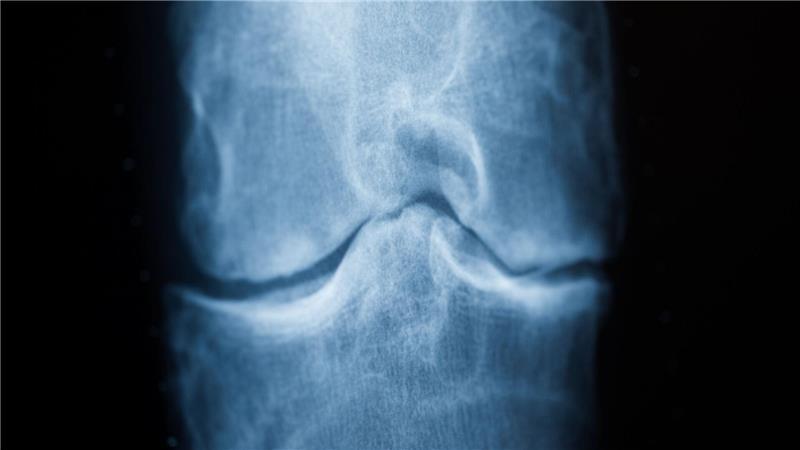

Spätestens das Röntgenbild schafft Klarheit: Der Knorpel nutzt sich immer mehr ab. Im späteren Stadium einer Arthrose reibt Knochen direkt auf Knochen. (Archivbild) Foto: Rolf Vennenbernd/dpa/dpa-tmn